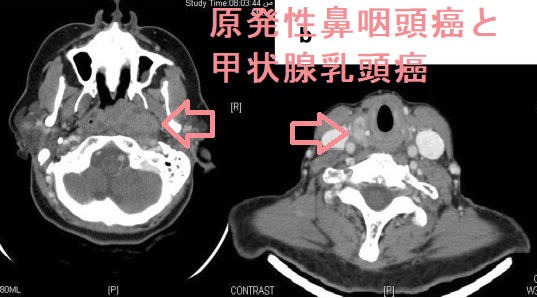

原発性鼻咽頭癌と舌扁平上皮癌甲状腺乳頭癌のトリプルキャンサーも報告されています(BMC Res Notes. 2013 Oct 28;6:432.)。

原発性鼻咽頭癌と甲状腺乳頭癌